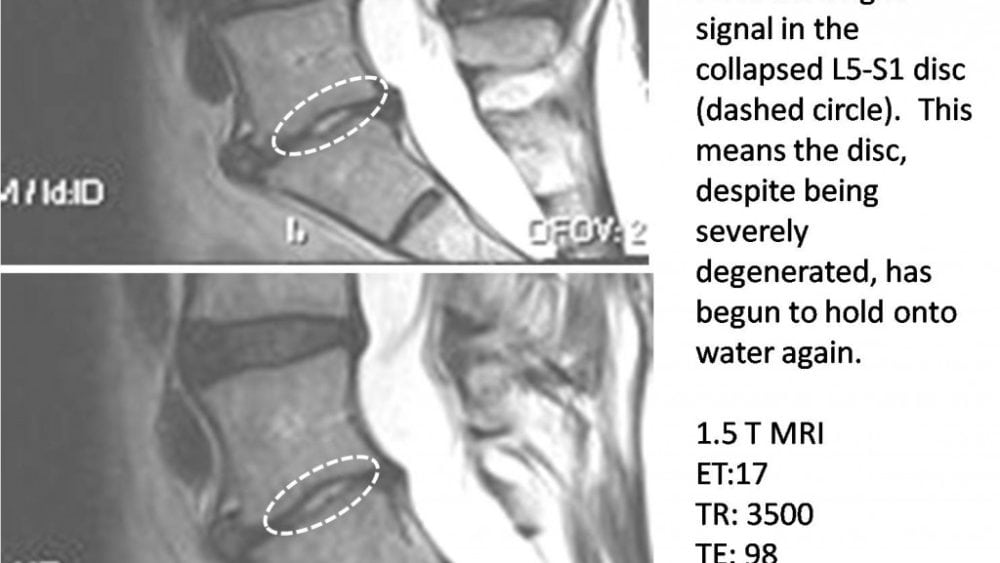

New Research on Stem Cells and Degenerated Discs

The title of the paper kind of hits you, “Mesenchymal Stem Cells Arrest Intervertebral Disc Degeneration…”.  This past week Chinese researchers published a paper showing that the same stem cell line being used in the Regenexx-C disc procedure can stop the natural progression of spinal discs from degenerating. This is similar to other papers…read more